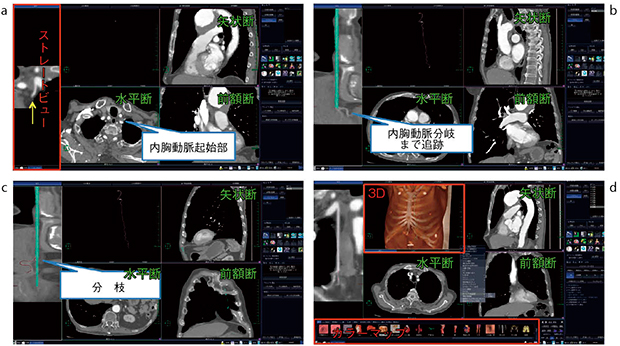

図1 内胸動脈解析ソフトによる抽出工程

a:CT水平断上にて内胸動脈の起始部をプロットする。

b:ストレートビュー上に自動抽出された内胸動脈を左ドラッグして左右に回転させ末梢まで追跡する。

c:再度,ストレートビュー上で抽出血管を回転させ,本幹から出る分枝をプロットし末梢まで追跡する。

d:内胸動脈抽出確定後,3D表示してカラーマップメニューから“心臓”を選択する。